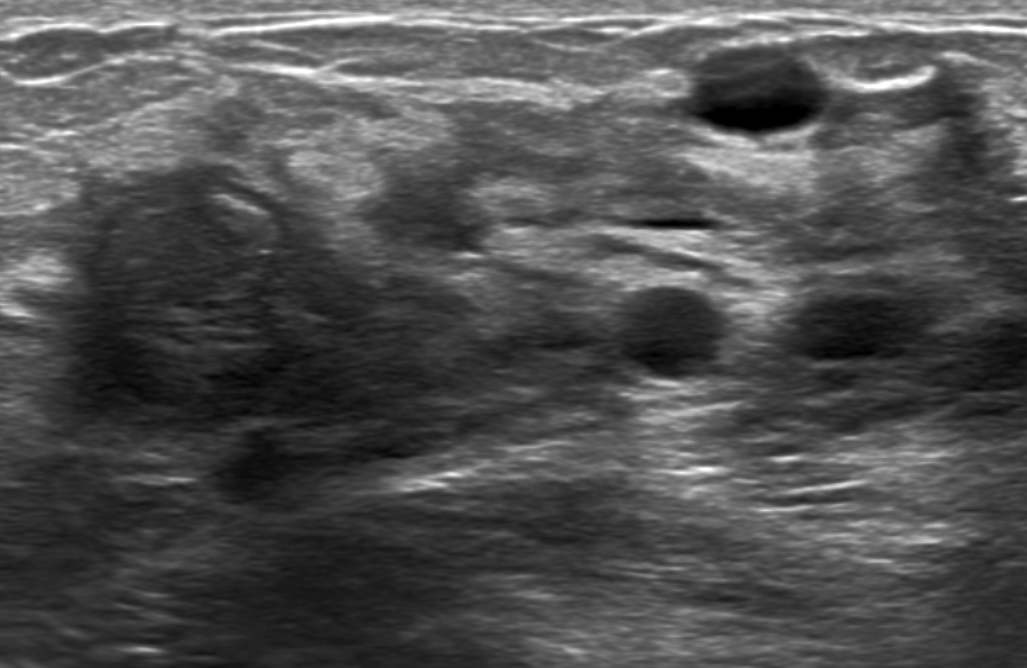

US

- Multiples kystes